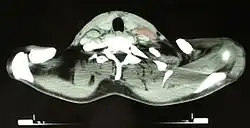

Диагноз

Основным критерием для постановки диагноза служит обнаружение гигантских клеток Рид — Березовского — Штернберга и/или клеток Ходжкина в биоптате, извлечённом из лимфатических узлов. Используются и современные медицинские методы: (ультразвуковое исследование органов брюшной полости, компьютерная рентгеновская или магнитно-резонансная томография органов грудной клетки). При выявлении изменений в лимфатических узлах необходима гистологическая верификация диагноза.

- Компьютерная томография, ПЭТ/КТ.